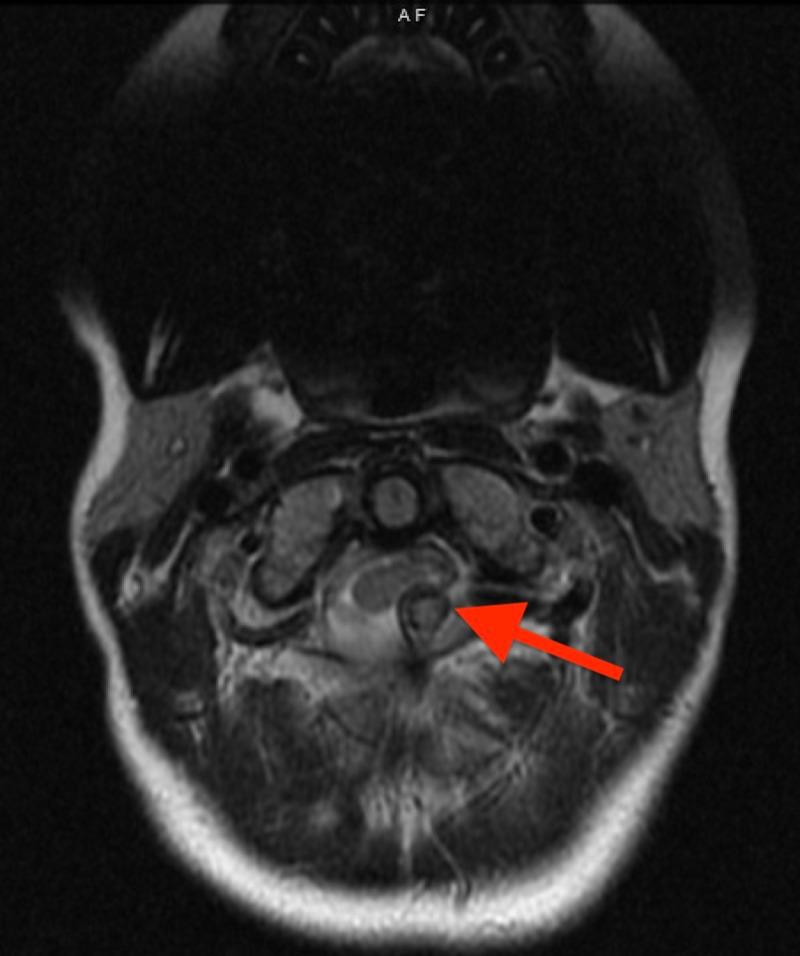

Background Multiple hereditary exostoses (MHE) is a rare disease characterized by multiple osteochondromas. Osteochondromas growing into the spinal canal can produce devastating consequences, including permanent neurologic deficits and even death. Routine screening of the entire spinal canal with magnetic resonance imaging (MRI) is a controversial topic lacking a clear consensus or recommendation to guide decision-making. This study presents a case of an intracanal osteochondroma at C1 identified by routine screening and a survey describing current practices of MHE experts. Methods MHE experts were surveyed. Survey questions addressed multiple aspects of care, including the type of practice center, the volume of patients with MHE, and current screening practices. Results A total of 104 experts were contacted, with a total of 26 experts participating in the survey and 23 completing the entire survey. Seventy-two percent of respondents do not perform a routine MRI screen of the spine. For experts that routinely screen, screening is performed across a wide/variable age range (4-18 years). Conclusion Screening protocols for MHE patients to identify osteochondromas within the spinal canal has struggled to reach consensus due to the rarity of the disease. Recent literature provides conflicting advice for patients without neurological symptoms. Our study demonstrates that even experts who are leading the field demonstrate wide practice variability. Most respondents do not routinely perform screening spinal MRI. Due to the wide variability, a national guideline is needed to help guide physician and parental decision-making for patients with MHE. Our case illustrates the potential benefit of identifying an osteochondroma within the spinal canal at a location where further growth could have devastating neurological sequelae.

背景 多发性遗传性骨软骨瘤(MHE)是一种以多发性骨软骨瘤为特征的罕见疾病。生长进入椎管的骨软骨瘤可产生严重后果,包括永久性神经功能缺损甚至死亡。使用磁共振成像(MRI)对整个椎管进行常规筛查是一个存在争议的话题,缺乏明确的共识或建议来指导决策。本研究报告了一例通过常规筛查发现的C1椎管内骨软骨瘤病例,并进行了一项调查以描述MHE专家的当前做法。方法 对MHE专家进行了调查。调查问题涉及护理的多个方面,包括执业中心类型、MHE患者数量以及当前的筛查做法。结果 共联系了104位专家,共有26位专家参与调查,23位专家完成了全部调查。72%的受访者不进行脊柱的常规MRI筛查。对于常规进行筛查的专家,筛查在较宽/可变的年龄范围(4 - 18岁)内进行。结论 由于该疾病罕见,MHE患者识别椎管内骨软骨瘤的筛查方案难以达成共识。近期文献对于无神经症状的患者提供了相互矛盾的建议。我们的研究表明,即使是该领域的领军专家,其做法也存在很大差异。大多数受访者不常规进行脊柱MRI筛查。由于差异很大,需要一个国家指南来帮助指导医生和家长对MHE患者的决策。我们的病例说明了在一个进一步生长可能产生严重神经后遗症的位置识别椎管内骨软骨瘤的潜在益处。